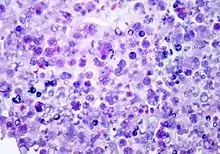

P. wickerhamii has a round to elliptical cell shape measuring 3–11 µm in diameter. The organism has thick wall (theca) with internal septations that form the small wedge-shaped endospores, which are arranged radially and moulded (morula-like form).[1] Reproduction is asexual by release of the spores from the sporangia, which can occur every 5–6 hours in ideal conditions.[2]

Diagnosis can be made through culture of diseased tissue in Sabouraud dextrose agar or by visualization of sporangia containing sporangiospores on tissue biopsy (using hematoxylin/eosin, GMS, or PAS histochemical stains). The organism incites a chronic granulomatous inflammation with infiltrate of histiocytes, lymphocytes, giant cells and occasional eosinophils.

Differential diagnosis: Protothecal sporangia may be confused with Coccidioides immitis, which are much larger